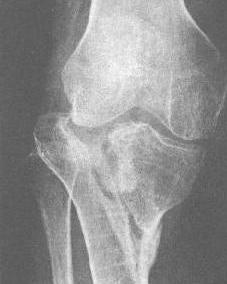

胫骨平台骨折[1](fracture of tibial plateau)是膝关节创伤中最常见的骨折之一。膝关节遭受内/外翻暴力的撞击,或坠落造成的压缩暴力等均可导致胫骨髁骨折。由于胫骨平台骨折是典型的关节内骨折,其处理与预后将对膝关节功能产生很大的影响。同时,胫骨平台骨折常常伴有关节软骨、膝关节韧带或半月板的损伤,遗漏诊断和处理不当都可能造成膝关节畸形、力线或稳定问题,导致关节功能的障碍。